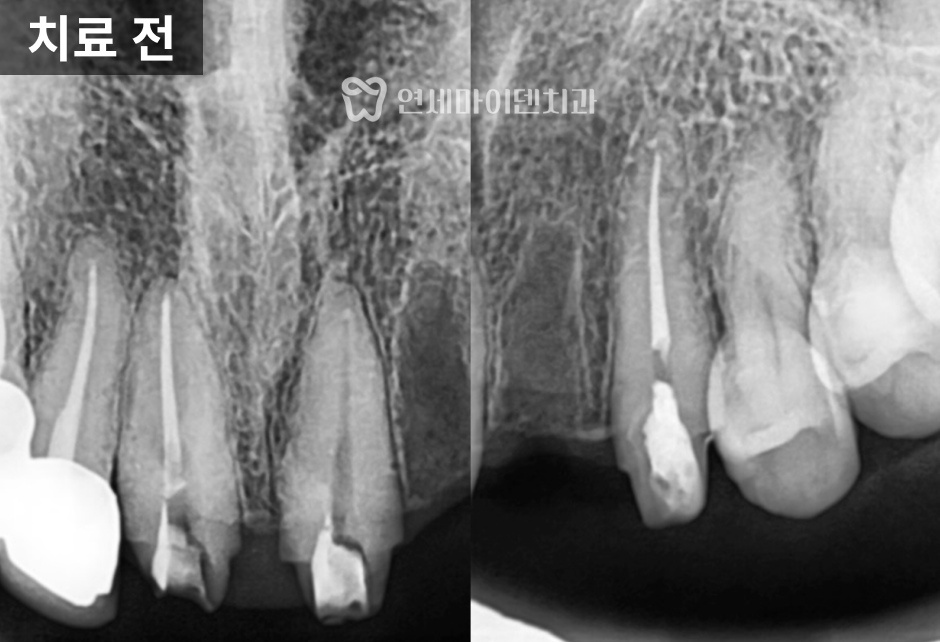

정밀 촬영 결과

두 개의 앞니 뿌리 끝, 즉 치근단 부위에서

뚜렷한 염증 소견이 확인되었습니다.한쪽 치아는

뼈 손상이 심해 예후가 불량한 상태였고,

다른 한쪽은

염증이 국소적으로 제한되어 있어

신경치료 후 경과를 지켜볼 수 있는 상황이었습니다.이에 따라 치료 계획은 다음과 같이 세웠습니다.

- 두 치아 모두 기존 보철물과 포스트를 제거

- 예후가 불량한 치아는 발치 후 즉시 임플란트 식립

- 살릴 수 있는 치아는 신경치료를 통한 보존